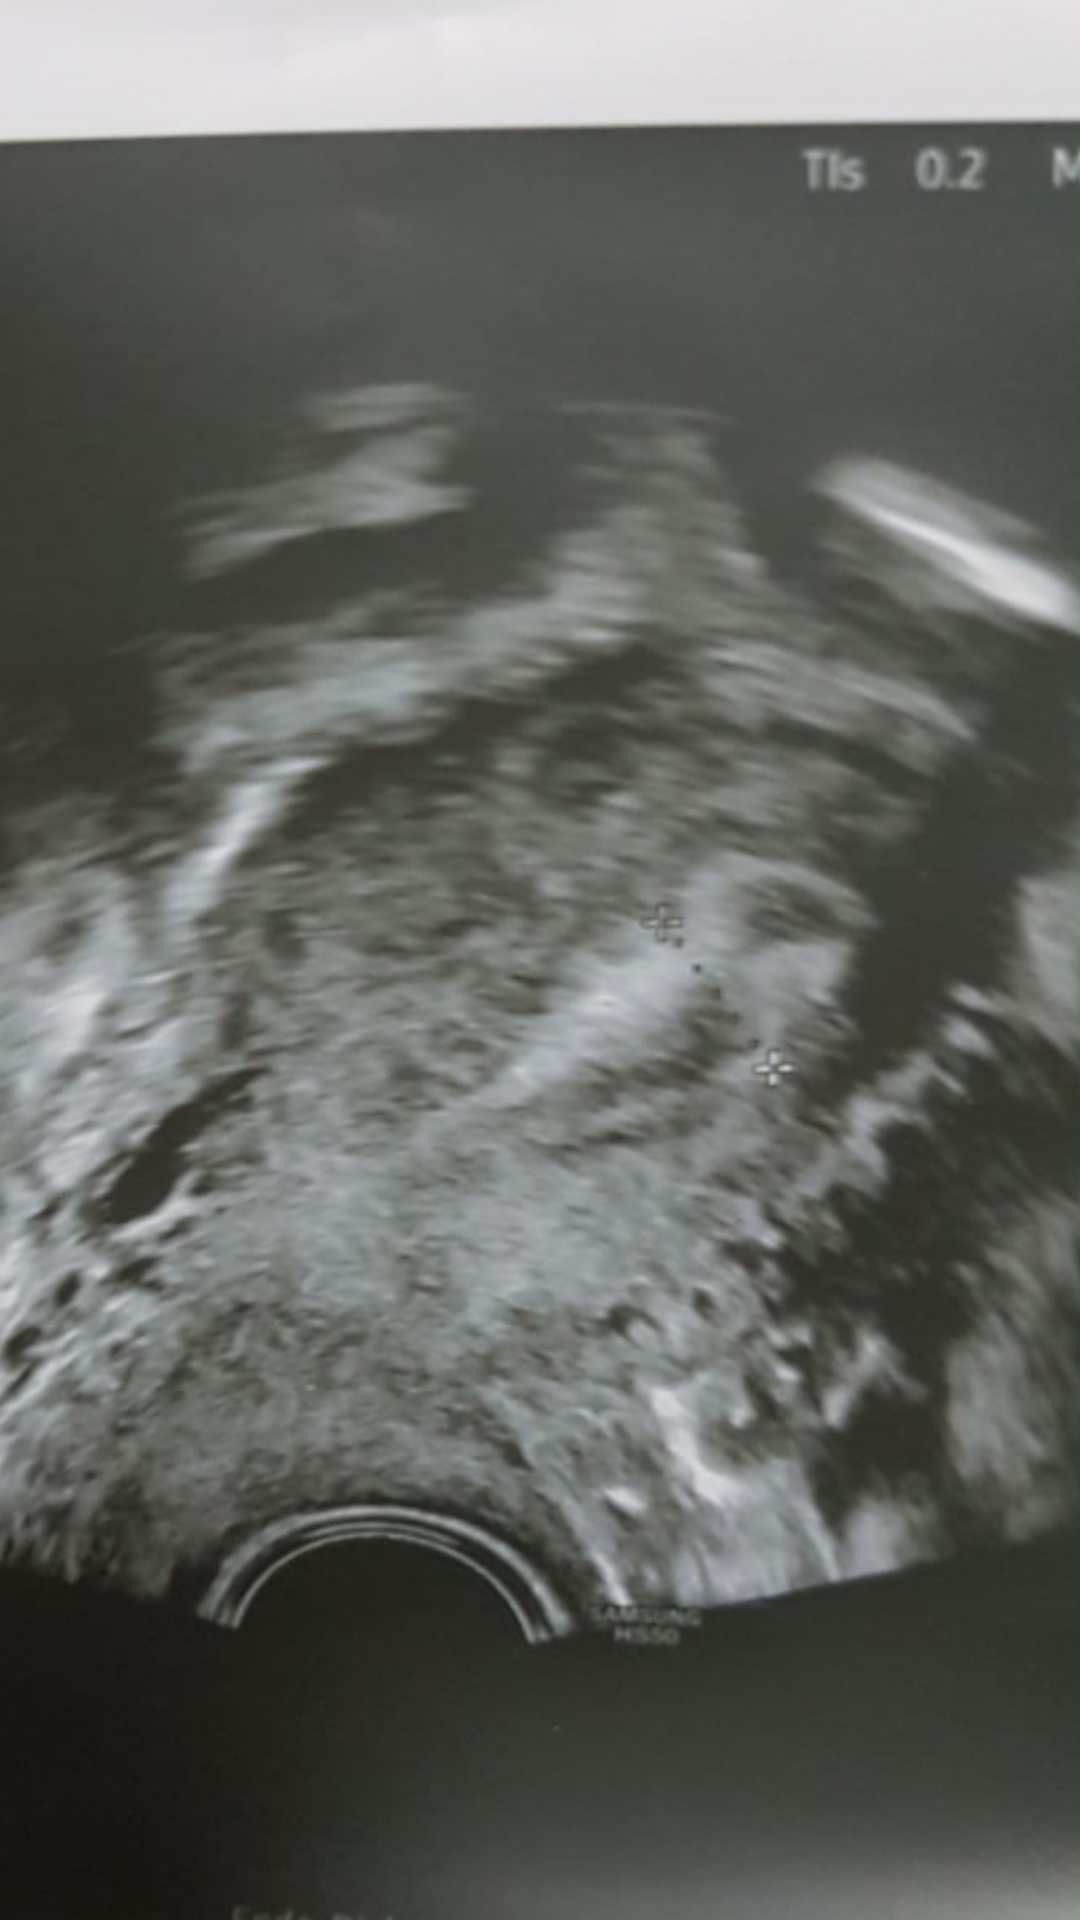

Ich hatte ein künstlichen kryo Transfer im Ausland. Mein FA in DE sagte an ZT9 dass er Progesteron geben würde für 5 Tage und den Transfer ansetzen würde, da Gbsh bei 8mm sei und sehr schön dreischichtig.

Mein FA sagte dann an diesem Termin, es sieht sehr schlecht aus, nicht mehr dreischichtig, 12.9 mm Schleimhaut, warum ich denn nicht vorher transferiert hätte. Jetzt rät er davon ab. Meine Schleimhaut hätte sich schon ins schlechte umgewandelt, es wäre was in Gange.Den Progesteron Wert kannte er aber zu diesem Zeitpunkt noch nicht, da das Bluteergebnis erst nachmittags da ist. Er lag dann bei 0.45 μg/l

Meinem Arzt im Ausland schickte ich die Ultraschallbilder und den Wert und sagte ihm dass es nicht mehr dreischichtig ist und mir abgeraten wurde.